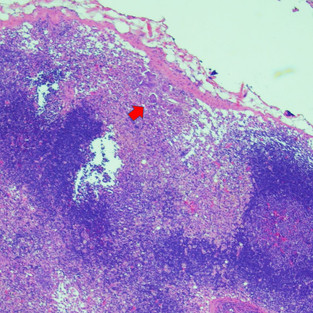

回想在大學時小編只知道乳腺腫瘤分成simple、complex跟mix type 隨著時代的演進 乳腺的分類也越來越詳細,然後越來越複雜 除腫瘤形態分型外 多數乳腺腫瘤可用Canine/ Feline histological grading criteria進行病理分級(分三級) 並藉由檢查腫瘤是否有淋巴結侵犯、血管侵犯或淋巴結轉移等惡性表徵 幫助臨床醫師作為臨床預後的參考